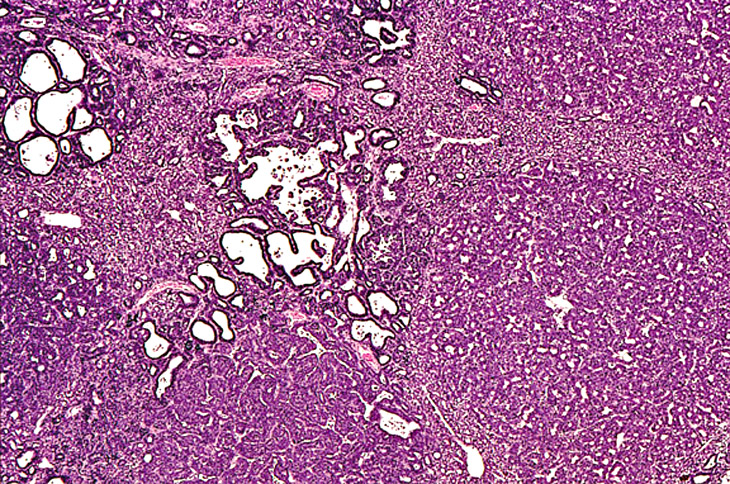

Juxtaposition of a bile duct adenocarcinoma and a hepatocellular adenoma in a 4-week-old transgenic mouse.

Anaplastic cytology is present in this hepatocellular carcinoma in a transgenic mouse.